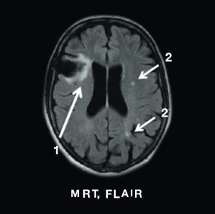

Neurologisch Untersuchungen unterteilen sich in bildgebende Verfahren wie die Magnetresonanztomographie (MRT) und Fragebögen insbesondere zu Schmerzen und der Lebensqualität. Hinzu kommt die Vorgeschichte der/des Patient:in, denn Schlafanfälle und transitorische ischämische Attacken (TIA) in jungem Alter (unter 55 Jahren) sind ein starker Hinweis auf Morbus Fabry.

Typische MRT-Befunde sind White Matter Lesions, Schädigungen der weißen Hirnsubstanz und Pulvinar-Zeichen, die sich als Hyperintensität unter T1-Wichtung darstellen. Fabry-Patienten leben oft dauerhaft mit Schmerzen unterschiedlicher Qualität, Intensität und Lokalisierung, dies kann durch standardisierte Fragebögen, z. B. den SF-36, dokumentiert werden.

MRT, FLAIR

mrt_03

1. Hirninfarkt cerebri media rechts

2. WML linke Hemispähre

Mit freundlicher Genehmigung von Prof. Dr. Arndt Rolfs, Universität Rostock